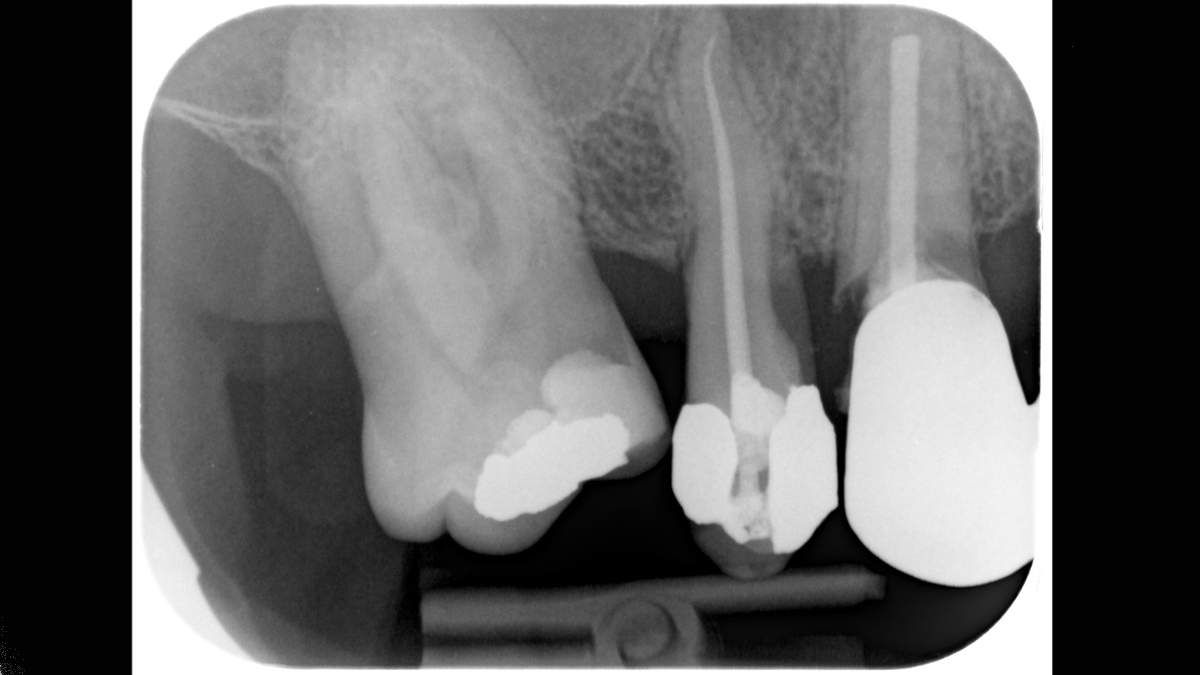

Xios Scan proporciona una introducción gentil y sencilla en el mundo de imágenes de rayos X digitales. Si desea cambiar de película a digital sin tener que renunciar a sus métodos de trabajo probados y reales, la tecnología de placa de imagen le ofrece un vistazo a las posibilidades. Puede experimentar muchas de las ventajas de la imagen digital sin salas oscuras y químicos mientras su equipo continúa con su flujo de trabajo normal.

Xios Scan se integra perfectamente con las unidades de rayos X de Dentsply Sirona y software para entregar diagnósticos intraorales más rápidos, seguros y mejores.